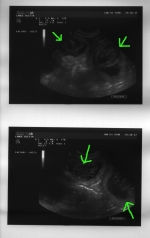

Fast drei Wochen sind seit dem ersten Ultraschall-Termin verstrichen und es läßt mir keine Ruhe - ist noch alles in Ordnung? Zu frisch ist noch meine Erinnerung, als wir die Wurfkiste schon aufgebaut hatten und dann doch keine Welpen kamen. Um meine Nachtruhe (und den Hausfrieden...) zu retten, waren wir heute erneut zum Ultraschall. Ich mochte ja kaum dran glauben - soll dieses Mal wirklich alles gut gehen? Bletta wird immer dicker, obwohl ihre Futterration sich nicht verändert hat, sie hat auch schon zugenommen. Der Ultraschall zeigt deutlich den Grund: Vier Welpen sind sofort zu erkennen, und es sieht aus, als winkten sie uns zu, so sehr zappeln sie herum. Der Berger ist halt keine ruhige Rasse, offensichtlich von Anfang an...

Ultraschall vom 03.01.2008